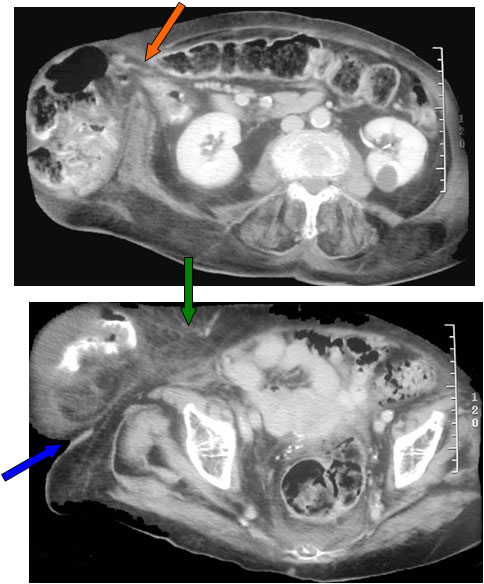

SIGNO DE LA PARED ABDOMINAL INCOMPLETA

Una masa situada en la pared abdominal, como por ejemplo una hernia, se caracteriza por presentar bordes incompletos, debido a que, en algún punto de su contorno, éste se confunde con los tejidos blandos adyacentes.

El ejemplo que mostramos corresponde a una hernia, de la que sólo es visible el margen inferior (flechas).

TC de abdomen con contraste oral e iv. del mismo paciente. La imagen superior muestra la herniación de asas intestinales (flecha naranja). La imagen inferior, correspondiente a un corte de pelvis, justifica el signo: un extremo del saco herniario forma un ángulo agudo con la pared abdominal (flecha azul) y es el borde visible en la radiografía; el otro extremo se continúa con la pared abdominal (flecha verde), lo que justifica la zona incompleta de la pared de la masa.